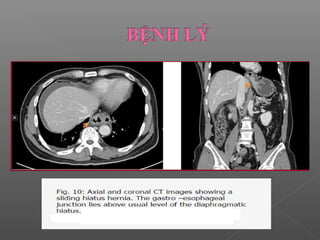

 Bất thường đường viền (Contour abnormalities):

Hay gặp

Nguyên nhân:

Hay gặp nhất là thoát vị dạ dày

Ít gặp: túi thừa dạ dày, lồng ruột.

 Bất thườngđường viền (Contour abnormalities): Hay gặp Nguyên nhân: Hay gặp nhất là thoát vị dạ dày Ít gặp: túi thừa dạ dày, lồng ruột.